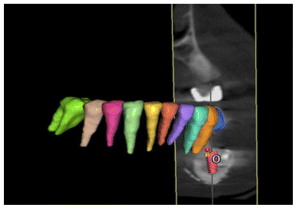

The maxilary and mandible were scanned with a Medit I500 Scanner, the lower scanning of the distal extensión of the mandible was difficult to obtain because of the mobility of the mucosa and the scanner lost the track. Conventional impressions were taken and an analog wax-up was made that gave us the ideal occlusion based on the antagonist, in the same way a digital wax made base don the analogic wax up, then the mandible and upper jaw were printed in stereolithography (Figs. 22, 23).

When analyzing the case in conjunction with the impression, the sterolithography, the digital scanning, waxing and position og the implants in the CT scan, it was observed that the ideal center of the crowns would be outside the prosthetic center, because the bone formed was not thick enough, the placement of the implants would have to be in a crossbite and try to correct it with milled and angled attachments. with screw-retained crowns to leave a better occlusion (Figs. 23, 24).

A surgical guide based in the analysis was elaborated for the the surgery. Three implants were placed in the new bone formation of the mandible, one in the premolar and two in the molars, Nobel Replace conical connection implants of 35 × 10 mm, 4.3 × 8 mm, 35 × 11.5 mm were used, a two-phase protocol was chosen, (Figs. 25, 26, 27).